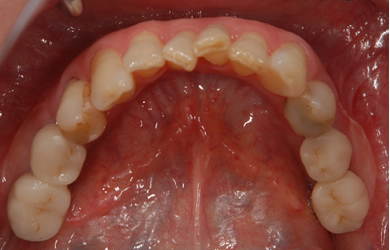

インプラントの症例写真 IMPLANT

スピードインプラント治療+セラミック治療

| 治療方針 | 抜歯と同時にインプラント治療を行うことにより、治療期間を短縮。 | ||||||||||||||||||||||||||||||||

| 治療内容 | インプラント4本(通常インプラント3本、抜歯即日スピードインプラント1本)、ハイブリッドセラミック5本 | ||||||||||||||||||||||||||||||||

| 総治療費 | 1,385,800円 | ||||||||||||||||||||||||||||||||

| 治療期間 | 4ヵ月+6ヶ月 |